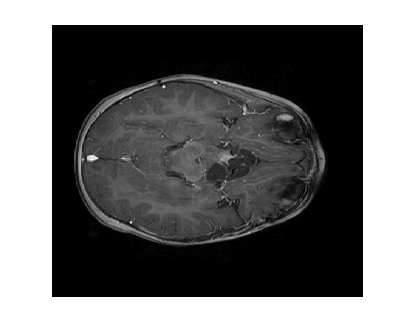

Figure 3 displays the reconstruction MSNR for the various test cases as cataloged in Table 1. Figures 1 and 2 display some examples of reconstructed images for cases of interest.

Due to its wide use in image processing, we consider the use of gradient sparsification with LACS-MRI. We show below that it is possible to produce image reconstructions with significantly higher Reconstruction SNR using gradient sparsification. We have repeated some of the simulations from above for different compression levels, , using the gradient transform to sparsify instead of the wavelet transform. We will refer to this as ”LACS-MRI with gradient sparsity.” We compared the performance of each sparsification method at each compression level using LACS-MRI and then compared this to the L1-W method. Again, we use a reference image and a follow-up image that we hope to recover as in Figure 8. We consider here only the phantom image, as it serves as a prime candidate for gradient sparsification, and is small enough that evaluation of all PDFs is computationally feasible.

We re-ran simulations for cases 7, 8, 17, and 18 on the phantom. Over 30 trials, using the gradient on the phantom image resulted in much higher RSNR for every single case. Cases 7 and 17 both also outperformed cases 8 and 18 every time by about 13%. These cases both used the variable density sampling method and LACS-MRI. Figure 9 shows the reconstruction from Case 17. The recovered image using LACS-MRI with wavelet sparsity is more pixelated near the tumor while LACS-MRI with gradient sparsity produced an almost perfect reconstruction. Figure 11 shows the great disparity between the two sparsifying methods. On average, the four phantom reconstructions using the gradient only needed to sample about 6% of the data to achieve the same RSNR that the reconstructions using the wavelets did at 21% sampling.

We also compare the LACS-MRI gradient method to the Cases 9 and 10 which use -minimization with wavelet sparsity. Clearly, the L1-W method recovered the phantom image very poorly, as shown in Figure 10 and Figure 11 (b). The image is blurry even when 18% of the available data was sampled. The RSNR of L1-W is worse than both the RSNR achieved by LACS-MRI with wavelet sparsity and LACS-MRI with gradient sparsity.